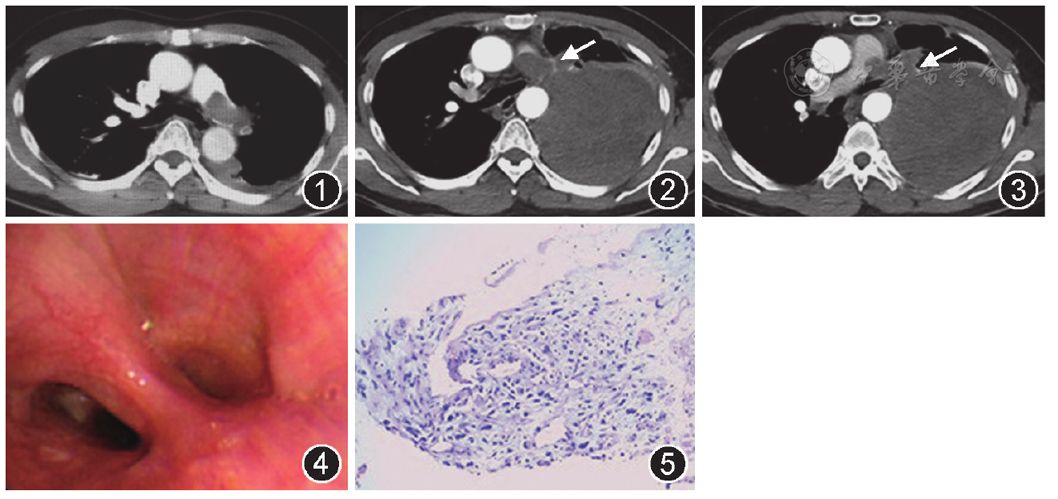

他45岁,冠脉造影发现血管严重狭窄,什么人才有必要做造影呢?做了冠状动脉造影,结果显示有一支动脉狭窄已经88%,为了防止冠脉闭塞,跟李先生及家属沟通后,在术中放置了一枚支架。目前一切状况良好。李先生是比较幸运的,他有异常症状的时候能及时就医,发现了狭窄后及时安放支架,预防冠状动脉突然阻塞导致的危险情况。 那么,临床上什么情...

o(?""?o 了解冠状动脉造影的优势:以下四个显著特点值得你关注许多医生会建议患者在临床上用冠状动脉造影进行检查。 不过冠状动脉造影是一种侵入性检查,会对身体造成损伤,一些患者可能会拒绝。可这种检查还是有很多优点的,在临床上也具有不可代替的作用。 第一、可以了解冠状动脉的情况 冠状动脉造影有助于检查体内血管是否阻塞或狭隘...